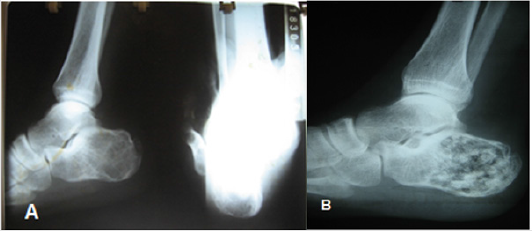

Figure 2:

A. Lesion at the calcaneus level showing osteolysis.

B. Filling of the lesion after curettage with incorporation of the bone graft.

Figure 3:

A. Osteolytic lesion at the level of the talus.

B. filling the lesion with cement (PMMA) and immediate rehabilitation of the patient.